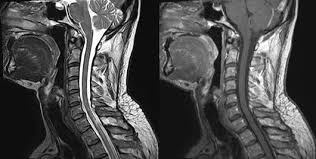

7 Wochen ein MRT der HWS mit der Diagnose Foraminastenose bds cervicaler Bandscheibenschaden Z.

Die Kernspintomographie ist für eine frühzeitige und verlässliche Diagnose von. Jahrelang wurde davon ausgegangen dass sich diese Veränderungen auf die weiße Gehirnsubstanz beschränken. Bei Zysten oder Vernarbungen im Bereich des Gehirns hindeuten. Wenn mehrere vernarbte Stellen größere Herde bilden spricht man von Plaques. Bei dem weißen Punkt rechts im Bild neben der Halswirbelsäule handelt es sich um eine Markierung auf der Haut die den Schmerzpunkt anzeigt. Es handelt sich um eine Schnittbild im coronaren Strahlengang parallel zur Stirn Der weisse Fleck ist ein Anschnitt der Aorta die dort einen Bogen macht. Ich weiß aber wie quälend es ist solange auf die Befundbesprechung zu warten. Ist die Aufnahme von vorne oder von hinten. Die Kernspintomographie ist für eine frühzeitige und verlässliche Diagnose von.

Bei Zysten oder Vernarbungen im Bereich des Gehirns hindeuten. Zur weiteren Differenzierung zwischen den Ursachen der Flecken sind Tests erforderlich die in der Regel durch einen Neurologen durchgeführt werden. Das Rückenmark als Schlüssel zur MS-Diagnostik. MRT der LWS T2 linkes Bild Weiß kann man die Entzündung der Lendenwirbelsäule erkennen da die Bandscheibe durch die Fehlstellung aufgebraucht wurde und nun Knochen auf Knochen reibt und eine Entzündung des Knochens entsteht. Ich habe viele mrt bilder von mir daheim. 7 Wochen ein MRT der HWS mit der Diagnose Foraminastenose bds cervicaler Bandscheibenschaden Z. Ein Computer wandelt diese Signalen in sichtbare Bilder um.